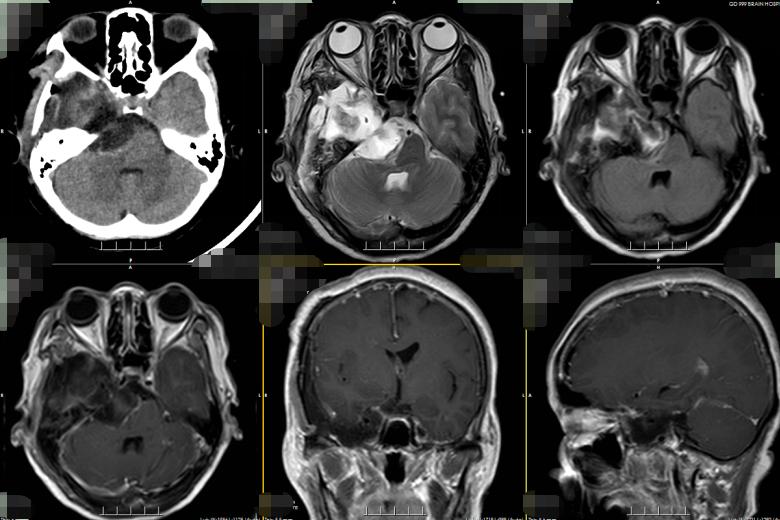

术后病理诊断为神经鞘瘤,证实吴杰术前的诊断。术后,群姐恢复得良好,症状也都消失,很快便出院了。

▲术后复查